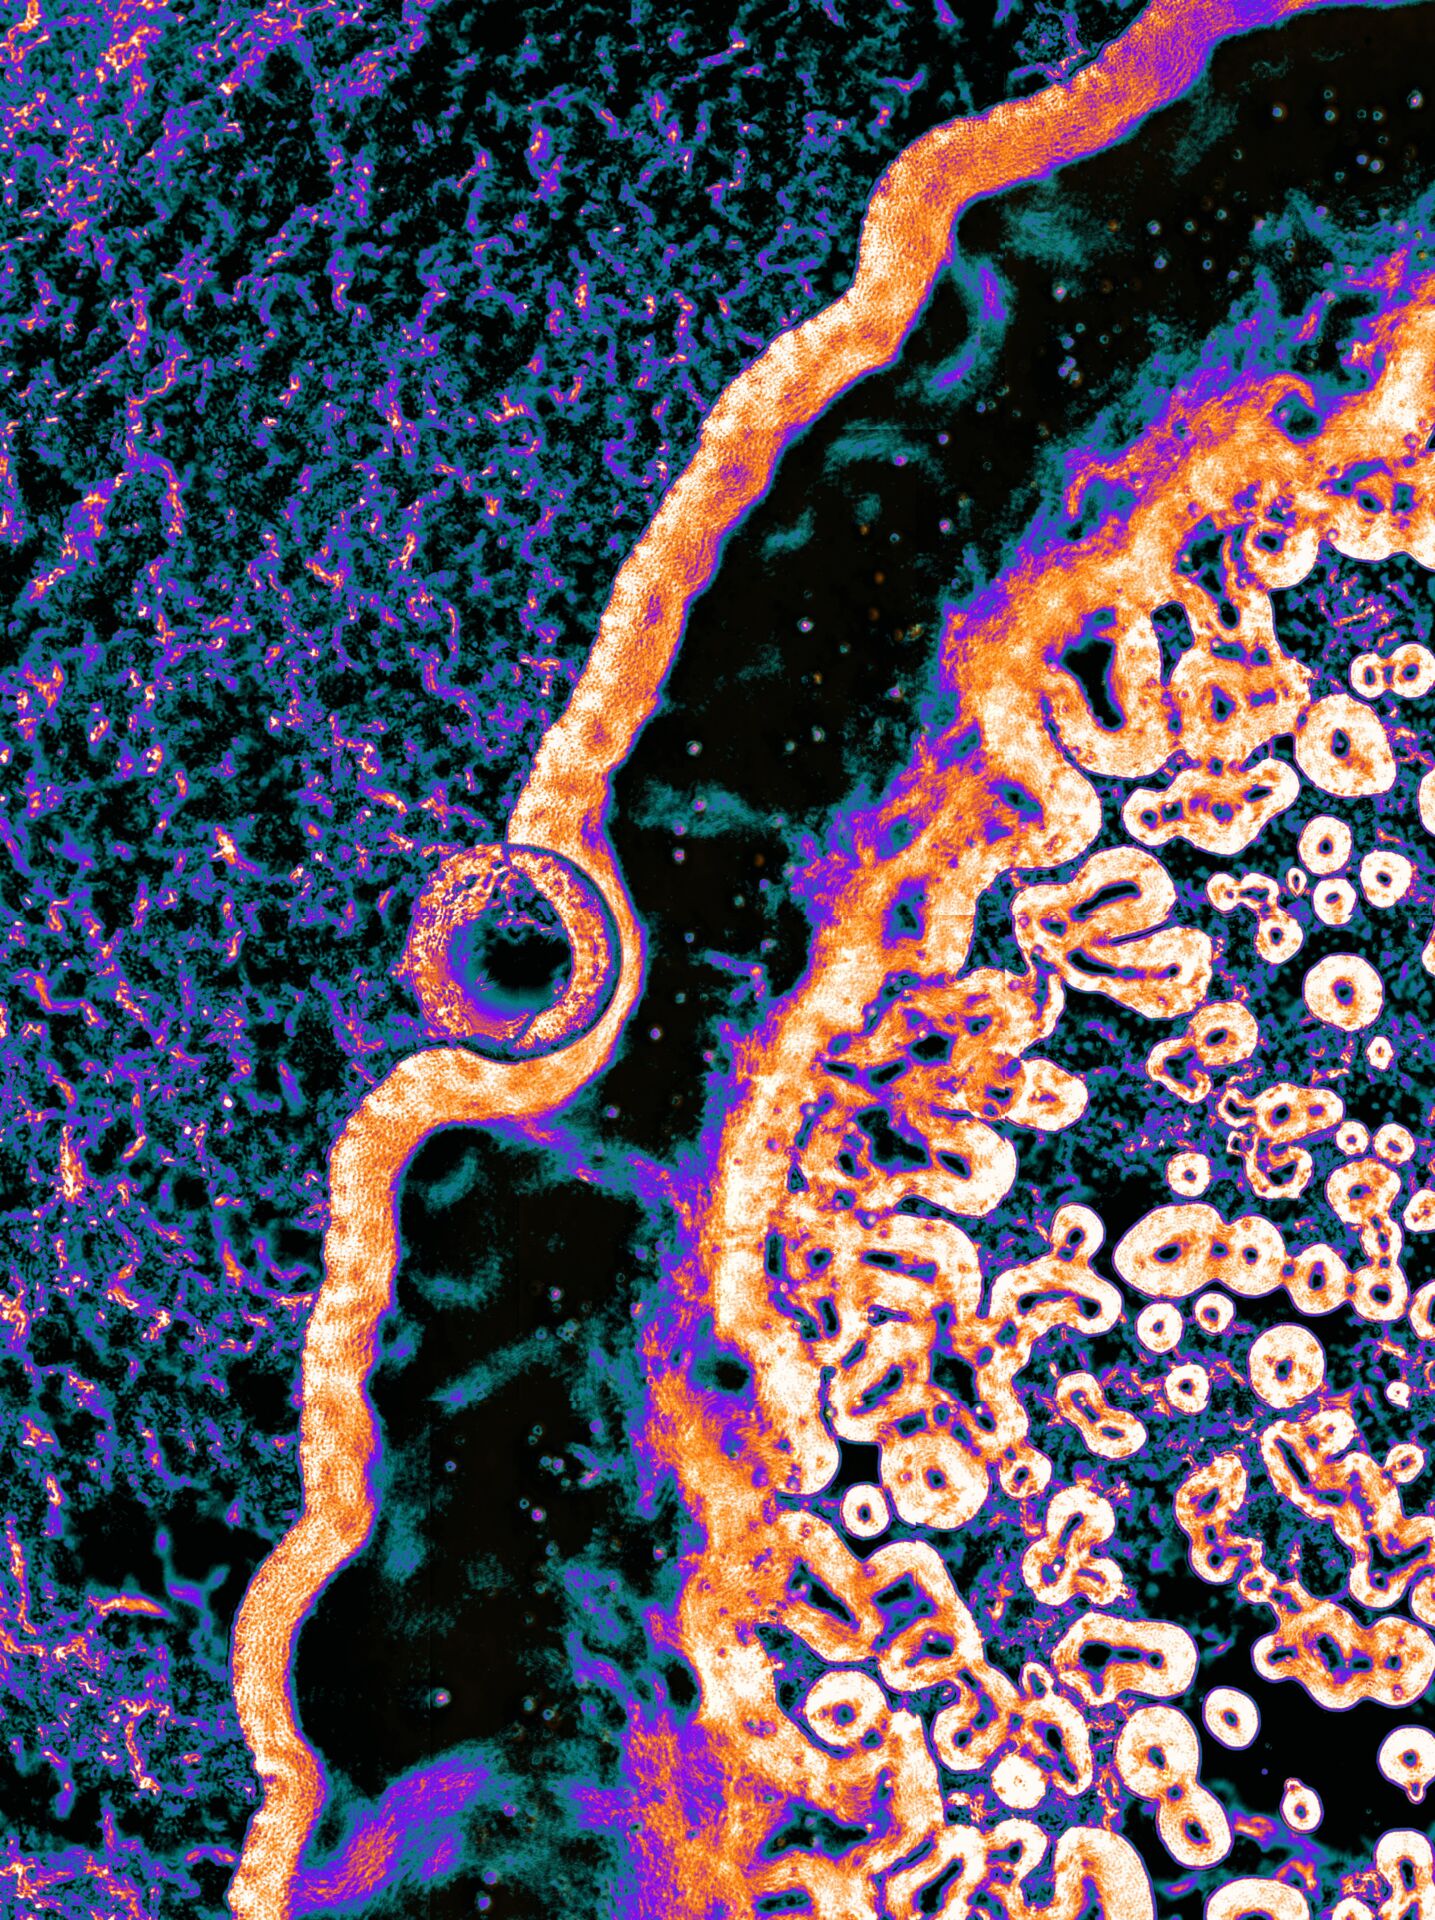

Kiril Kalenderski, University of Nottingham

Clinical biomineralized biofilm formed on a urinary catheter device

A coloured environmental scanning electron microscope image (ESEM) of a biomineralized biofilm formed on a clinical urinary catheter device. Struvite minerals are coloured in orange, apatite minerals are coloured in yellow, and the biofilm structure is coloured in purple. Magnification- 500x. Image Production: Kiril Rosenov Kalenderski and Nicola Weston. Nanoscale and Microscale Research Centre, University of Nottingham.